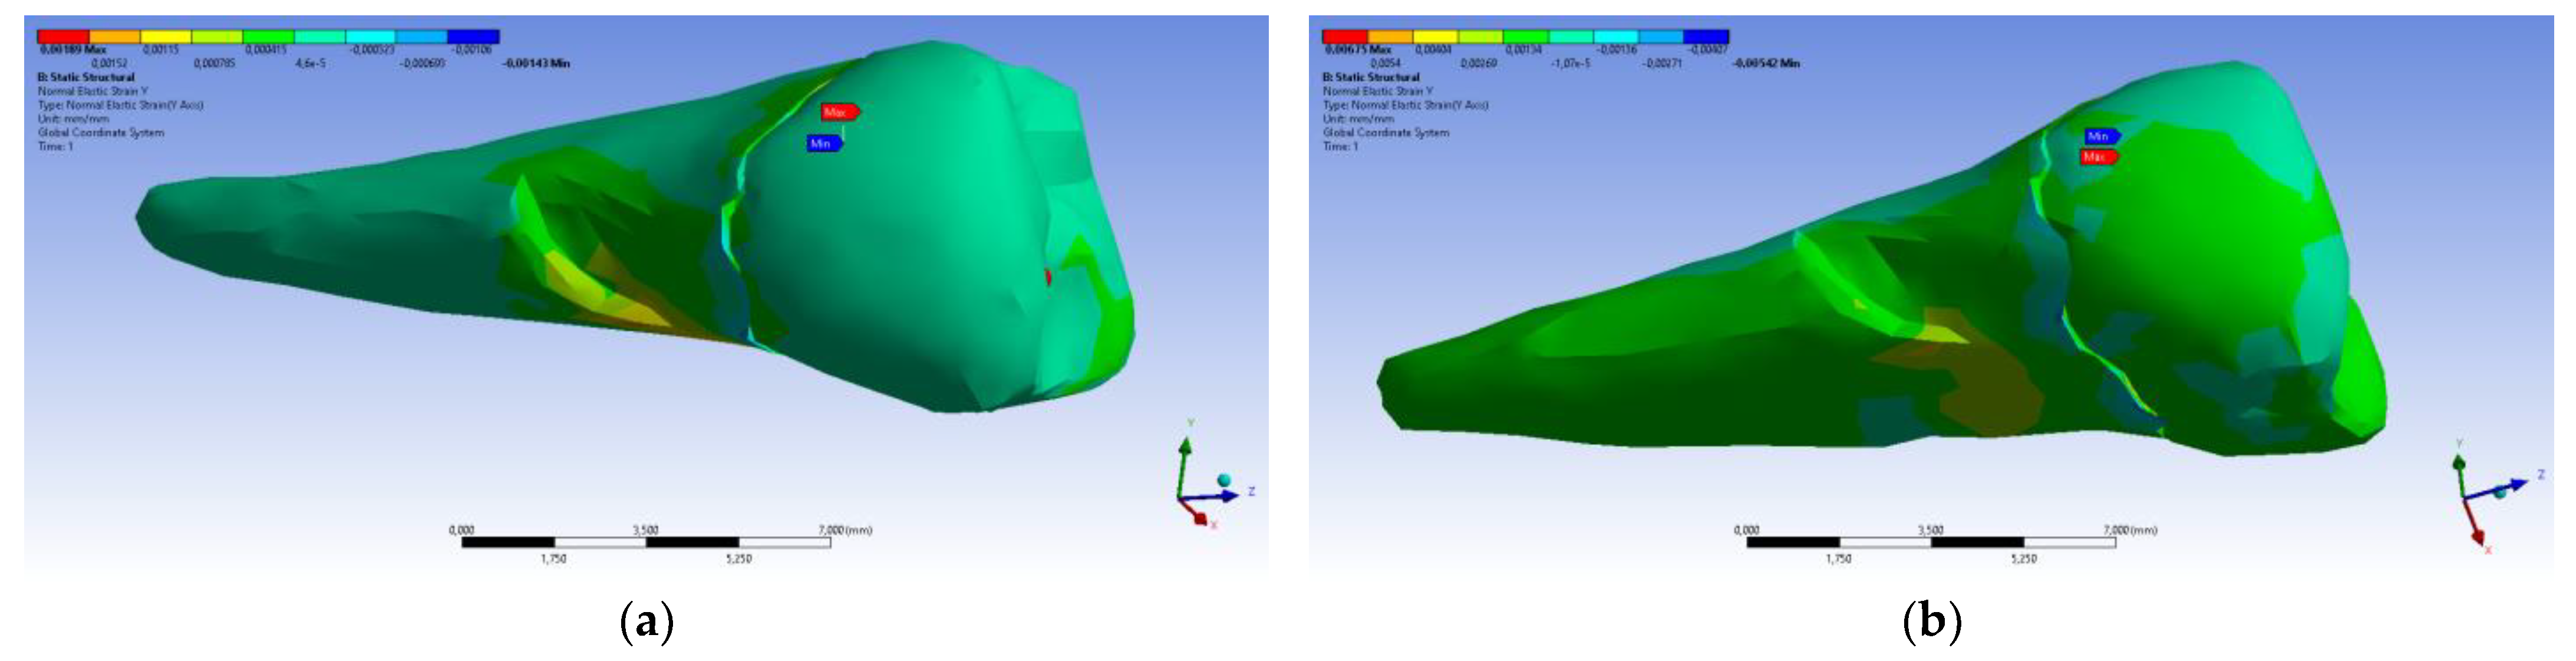

3. Finite Element Analysis (FEA) of Mandibular Right Premolars

| Maximum Tangential Stress | Main Elastic Relative Deformation | Main Maximum Elastic Relative Deformation | Main Minimum Elastic Relative Deformation | Maximum Tangential Elastic Relative Deformation | Relative elastic Normal X Deformation | Relative Elastic Normal Y Deformation | Relative Elastic Normal Z Deformation | Relative Elastic Tangential XY Deformation | Relative Elastic Tangential YZ Deformation | Relative Elastic Tangential XZ Deformation | |||

| Minimum | 5.4 × 10−7 MPa | 6.36 × 10−11 mm/mm | −1.33 × 10−5 mm/mm | −1.05 × 10−2 mm/mm | 7.6 × 10−11 mm/mm | −2.26 × 10−3 mm/mm | −1.43 × 10−3 mm/mm | −3.45 × 10−3 mm/mm | −2.81 × 10−3 mm/mm | −4.09 × 10−3 mm/mm | −7.93 × 10−3 mm/mm | ||

| Maximum | 143 MPa | 1.33 × 10−2 mm/mm | 9.66 × 10−3 mm/mm | 1.09 × 10−5 mm/mm | 2.01 × 10−2 mm/mm | 1.37 × 10−3 mm/mm | 1.89 × 10−3 mm/mm | 3.14 × 10−3 mm/mm | 6.23 × 10−3 mm/mm | 1.65 × 10−2 mm/mm | 3.13 × 10−3 mm/mm | ||

| Minim. in | Cementum | Cementum | Enamel | Cementum | Cementum | Cementum | Cementum | Cementum | Cementum | Cementum | Cementum | ||

| Maxim. in | Cementum | Cementum | Cementum | Cementum | Cementum | Cementum | Cementum | Enamel | Cementum | Cementum | Cementum |